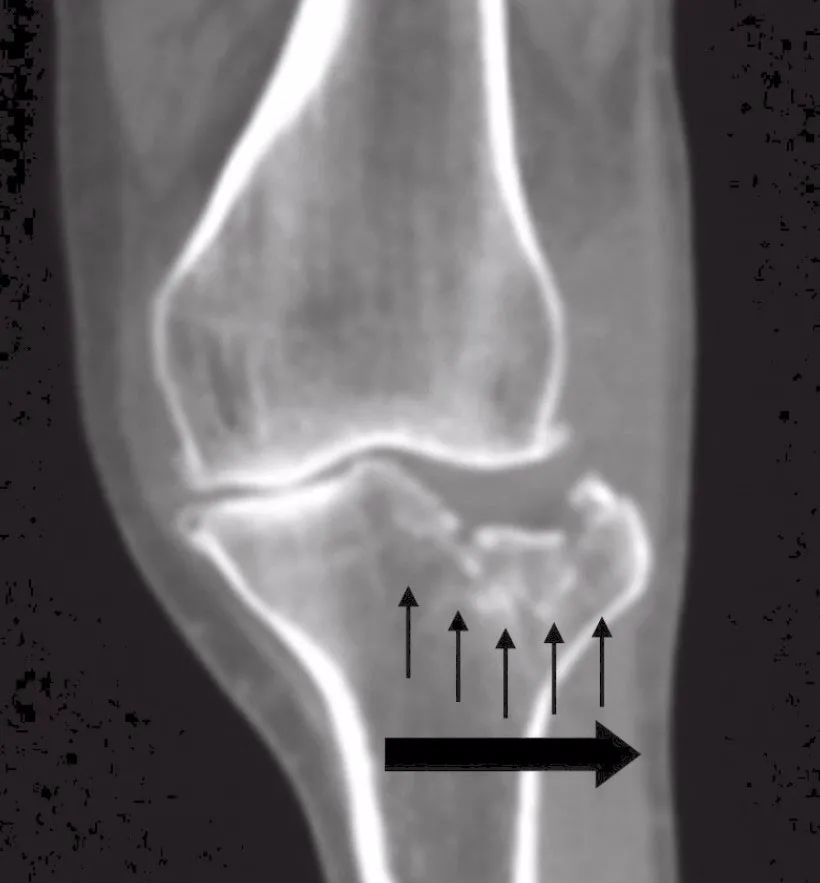

在撞击时,胫骨内侧髁凹面在大面积上吸收了冲击力,从而导致内侧髁纵向劈裂。另一方面,外侧髁凸面在吸收冲击力上为相对点接触,导致关节内塌陷(图1)。

图1 力学分布情况

罗从风等2010年以高能量骨折(Schatzker V型和VI型)的术前CT扫描为依据,描述了三柱分型。在横向或轴向视图,胫骨平台分为三个区域,定义为外侧柱、内侧柱和后柱(图3)。

这三柱在轴向切面被三条任意线所分隔。一种独立的关节塌陷伴柱皮质破坏定义为相关柱骨折。而像SchatzkerIII型一样的单纯关节塌陷骨折,定义为0柱骨折。尽管是为了用于高能量骨折分类,该分型同样可以推演到低能量损伤。这种分类不单单是为了进行骨折分型,它还能帮助选择手术处理方式。